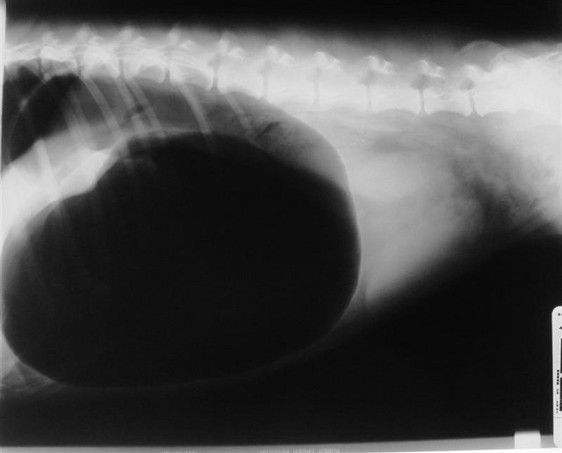

Radiography - GDV